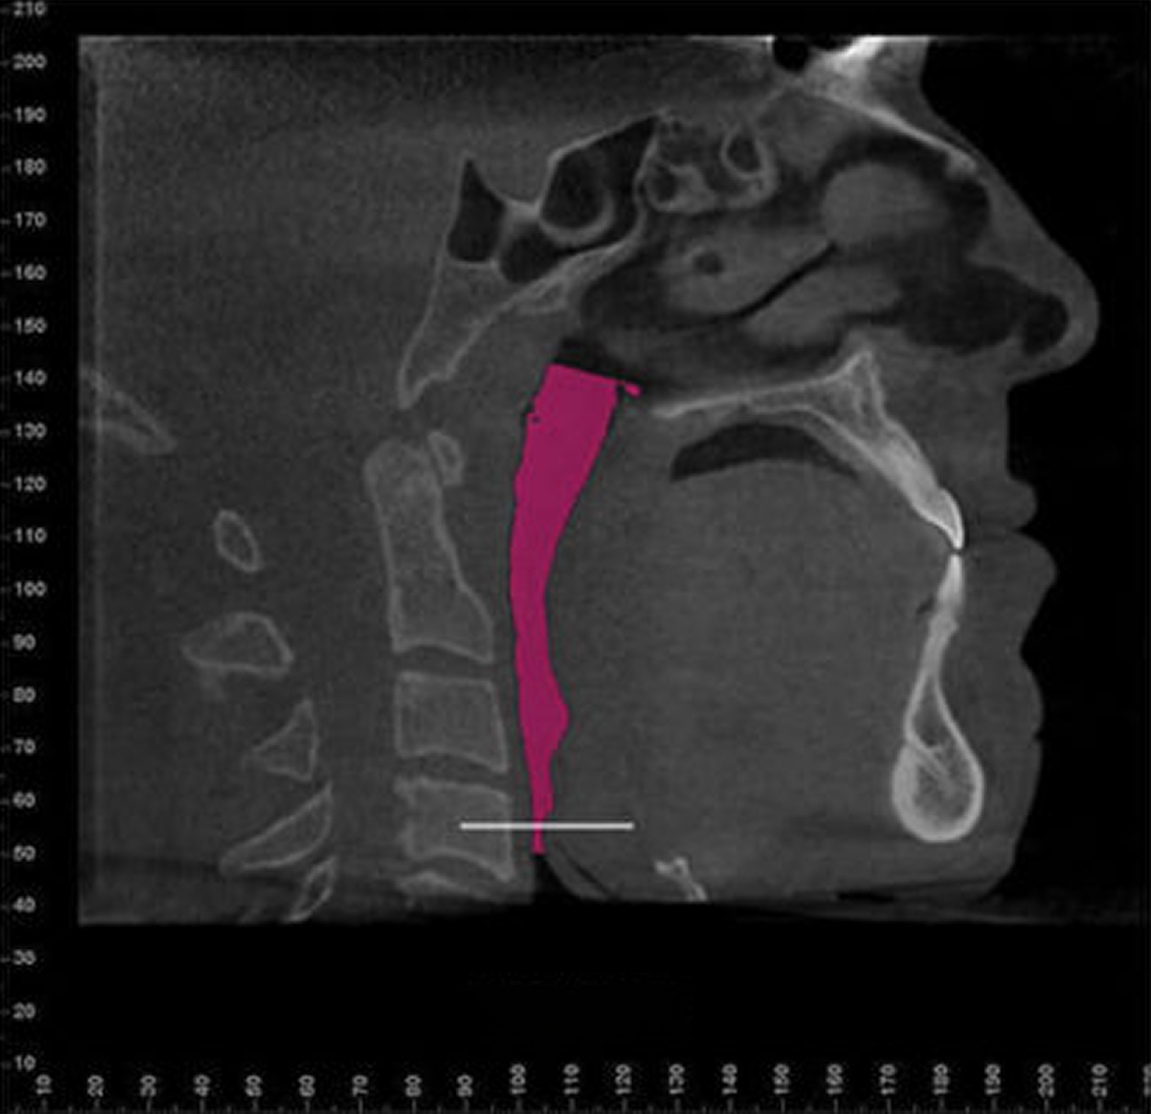

For many patients, an orthodontic intervention in Highland, NY or Ramsey, NJ can improve and sometimes eliminate these risks. Below are pictures of an OSA patient that benefitted from orthodontic treatment’s life-changing effects at Van Vliet & Ganz Orthodontics.

867% Airway Enhancement